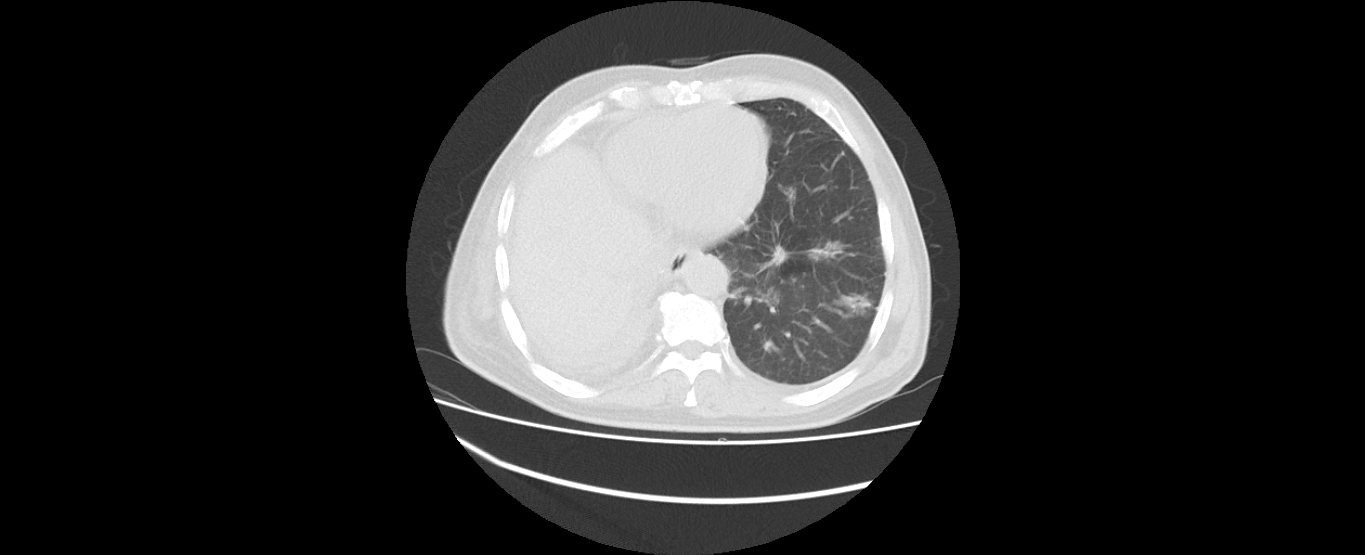

患者刘某某,男,60岁,因“右下肺中央型肺癌”2008年6月在外院行“右下肺癌根治术+右上肺部分切除术”,术后行化疗和放疗。2011年4月复查CT提示肿瘤复发,行化疗及靶向药物治疗,肿瘤控制;2016年8月新发肺转移,再次行化疗及靶向治疗,辅助中医药治疗,2017年2月复查,病情平稳。目前患者生活质量较好,没有不适症状,按时返院复查。

2016年8月